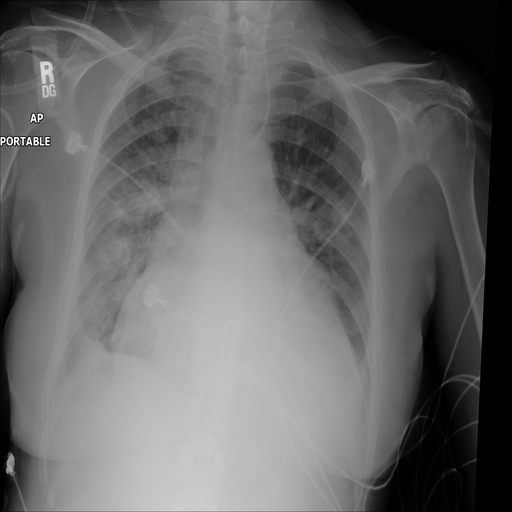

Purpose: Interpreting chest radiographs (CXR) remains challenging due to the ambiguity of overlapping structures such as the lungs, heart, and bones. To address this issue, we propose a novel...

In this work, we leverage the shared imaging properties between CXR and CTs to enable networks to delineate anatomical structures pixel-wise. The used PAX-Ray++ dataset has 157 anatomical classes with more than ten thousand images and two million annotated instances.

The anatomy in chest radiographs (CXR) is typically difficult segment manually due to the ambiguity introduced by overlapping structures. We Adress this in our paper and publish models to segment 157 anatomical labels in CXR: https://t.co/rsxUKoyvC5

When annotating such findings, however, it is also worth thinking about, do we want to capture the entire abnormal organ or just the part of the organ that is abnormal. Cardiomegaly in CXR is obv not a strong example, but still ...

I've been going over the saliency maps of our CXR Vision-Language model from MICCAI22. Despite it being somewhat obvious, I found it interesting that for some classes it will just activate on the abnormal enlargements for cardiomegaly. Other CNN had activated on the entire heart.